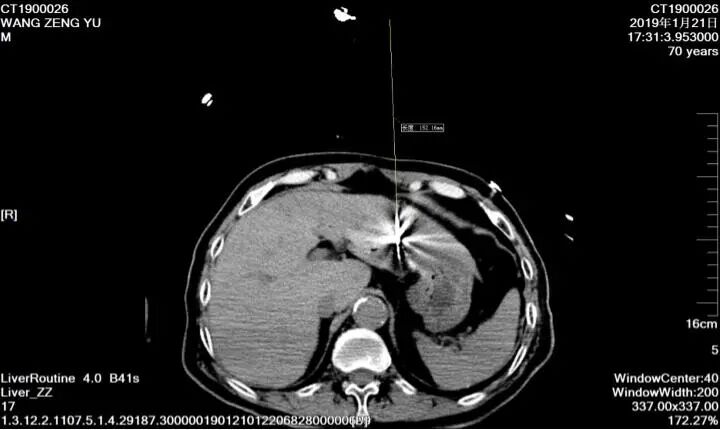

73歲男性,巨塊型肝癌,失去手術(shù)機(jī)會(huì),多次介入治療并聯(lián)合靶向治療,長(zhǎng)期帶瘤生存。

67歲女性,結(jié)腸癌術(shù)后肝轉(zhuǎn)移,行微波消融術(shù)將肝臟轉(zhuǎn)移灶清除,之后多次化療聯(lián)合免疫治療,目前病情控制可。

70歲肝癌患者,拒絕手術(shù)治療,經(jīng)射頻消融術(shù)治療,目前病情穩(wěn)定。